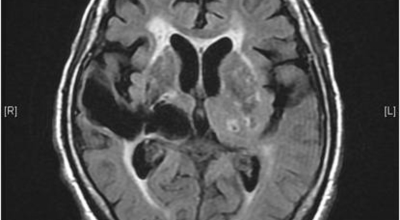

뇌경색의 경색이란 허혈성 괴사를 말해요. 여기서 허혈이란 혈관이 막히는 것을 말하고 괴사는 말 그대로 일부가 죽는 것을 말하는데 뇌경색의 경우 뇌의 혈관이 막혀 뇌세포 일부가 죽는 걸 의미해요. 뇌혈관이 막혔다 해서 혈액 공급이 안되는것은 또 아니에요.

막힌 혈관으로도 혈액이 공급되긴 하나 혈관이 막혀있어 혈액을 보내긴 하나 제대로 흐르지 못하고 혈액이 쌓이고 축적되어 물풍선에 물이 꽉 차서 터지듯 뇌혈관이 터지는 경우가 일어날 수 있는데 이를 뇌출혈 이라고 해요. 물론 외상으로 인한 뇌출혈도 있지만 이처럼 뇌경색으로 인해 혈관이 막혀 터지는 경우도 있어요.